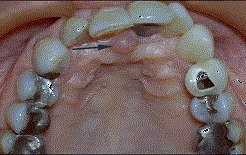

问题 无牙颌患者的口内特征为 ( )

选项 A.牙列缺失 B.牙列缺损 C.牙冠缺损 D.牙体缺失 E.牙体缺损

答案 A